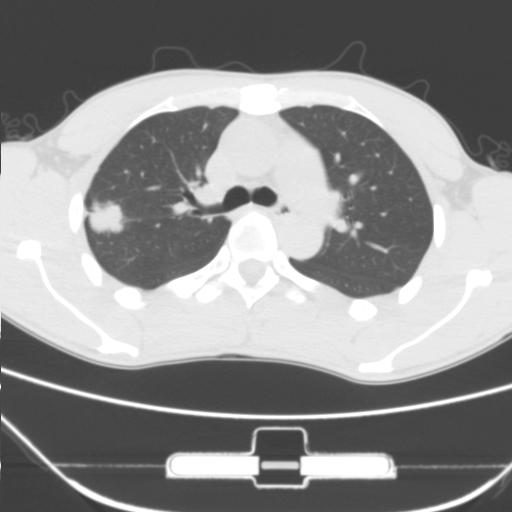

右肺上叶后段近胸膜下结节样异常密度灶,似见分页及毛刺,考虑右肺上叶周围型肺ca,建议穿刺病理检查

缺乏病史,症状体征,但这个孤立结节具备了几乎所有的恶性征象:分叶,毛刺,空泡征,胸膜凹陷征,血管集束。

考虑右肺上叶后段周围型肺癌。